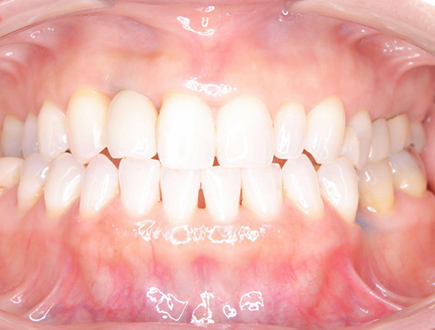

| 治療部位 | 上顎前歯部 |

|---|---|

| インプラント本数 | 4本 |

| 単価 | 40万円/本 |

| 合計費用 | 160万円 |